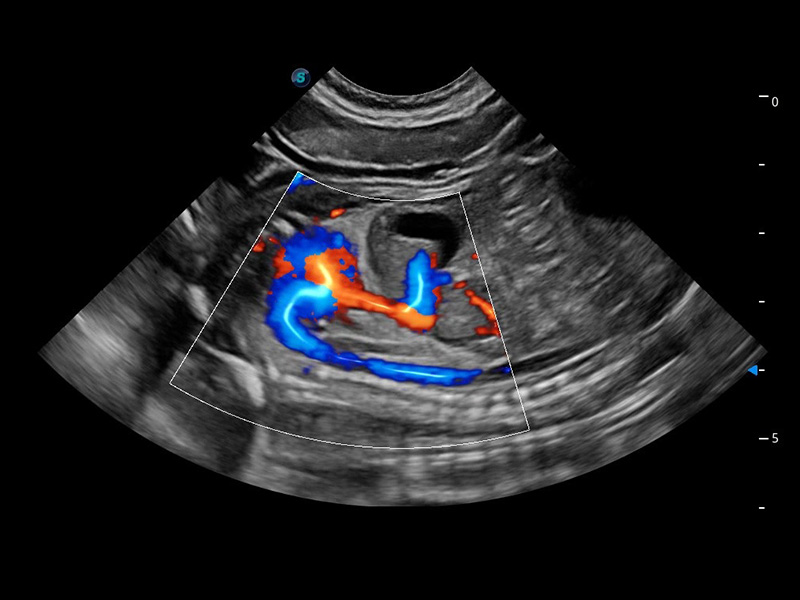

优异的基础图像

(猫)髂动脉血流频谱